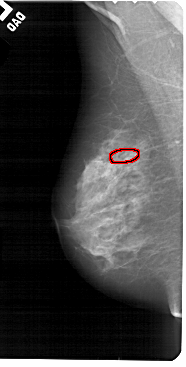

A_1553_1.RIGHT_CC

FILE: A_1553_1.LEFT_CC.OVERLAY

TOTAL_ABNORMALITIES 1

ABNORMALITY 1

LESION_TYPE CALCIFICATION TYPE PUNCTATE DISTRIBUTION LINEAR

ASSESSMENT 4

SUBTLETY 1

PATHOLOGY BENIGN

TOTAL_OUTLINES 1

BOUNDARY